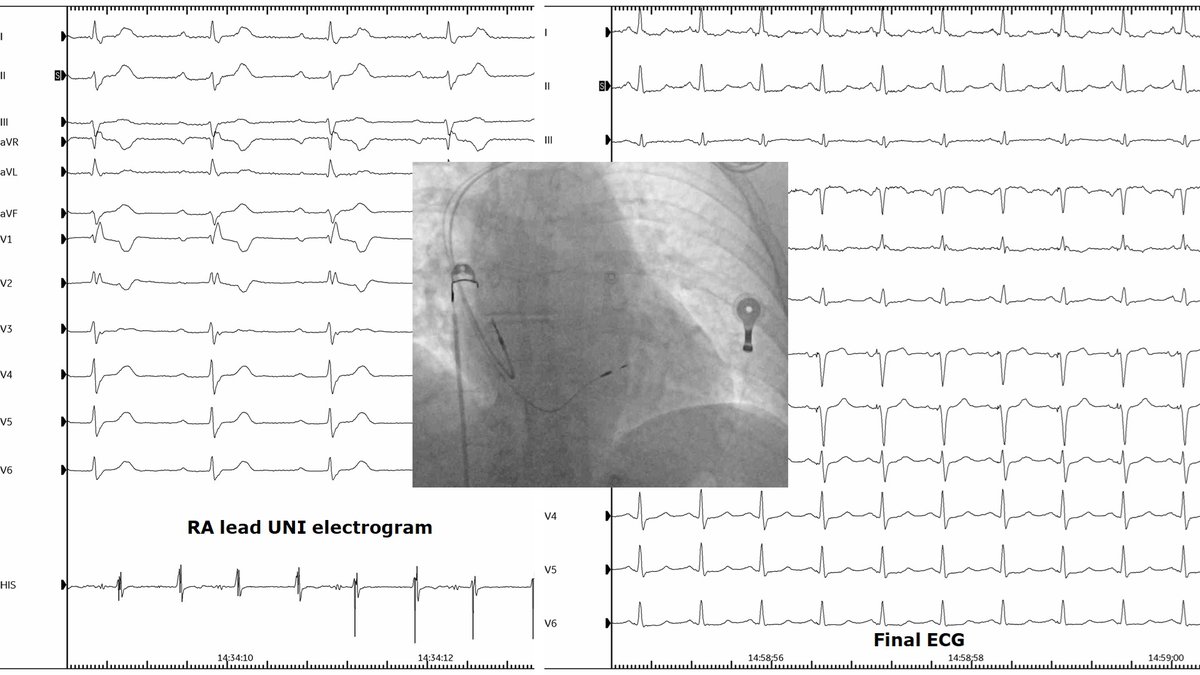

Celebrating 1yr since the publication of our Atlas of ConductSystemPacing #LBBAP #HBP! Thanks @ilpensiero for their support & to the readers for their trust! I hope it has been (& will be) useful to become confident in recognizing #CSP in your procedures! tinyurl.com/CSPAtlas